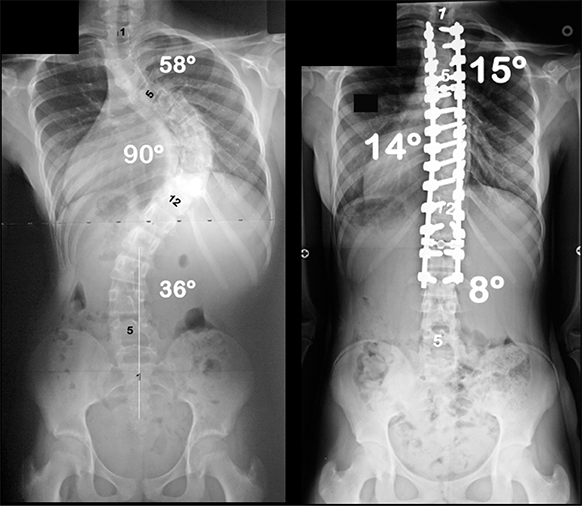

Spondylolisthesis suggests instability of the spine and can produce stenosis (abnormal narrowing of the spinal canal), pain, and sometimes nerve injury. Figure 7 (left): X-ray showing a lateral view (from the side) of a normal spine. Figure 8 (right): X-ray showing anterior spondylolisthesis, also known as anterolisthesis.

What is fusion surgery?

In fusion surgery, the vertebrae are essentially "welded" together, with screws or other instrumentation being used to secure and immobilize the bone.